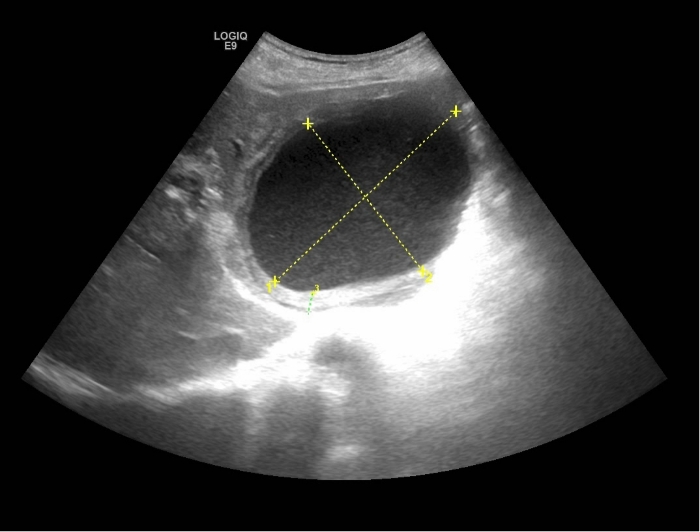

肝囊腫伴感染——囊內(nèi)沉積物

一名73歲的男性,因腹痛、發(fā)熱4天,來我院消化內(nèi)科就診。經(jīng)查體,患者以中上部腹痛為主,體溫最高39.0℃。腹部彩超檢查顯示,肝左葉可探及大小約108x79mm的巨大囊性回聲,擠壓周圍正常肝組織和血管,內(nèi)部“灰蒙蒙”的。